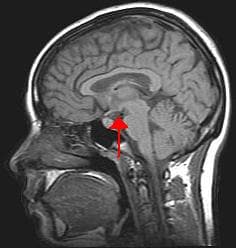

The hypothalamus () is a part of the brain that contains a number of small nuclei with a variety of functions. One of the most important functions is to link the nervous system to the endocrine system via the pituitary gland. The hypothalamus is located below the thalamus and is part of the limbic system. In the terminology of neuroanatomy, it forms the ventral part of the diencephalon. All vertebrate brains contain a hypothalamus. In humans, it is the size of an almond. The hypothalamus is responsible for regulating certain metabolic processes and other activities of the autonomic nervous system. It synthesizes and secretes certain neurohormones, called releasing hormones or hypothalamic hormones, and these in turn stimulate or inhibit the secretion of hormones from the pituitary gland. The hypothalamus controls body temperature, hunger, important aspects of parenting and maternal attachment behaviours, thirst, fatigue, sleep, and circadian rhythms. The hypothalamus is divided into three regions (supraoptic, tuberal, mammillary) in a parasagittal plane, indicating location anterior-posterior; and three areas (periventricular, medial, lateral) in the coronal plane, indicating location medial-lateral. Hypothalamic nuclei are located within these specific regions and areas. It is found in all vertebrate nervous systems. In mammals, magnocellular neurosecretory cells in the paraventricular nucleus and the supraoptic nucleus of the hypothalamus produce neurohypophysial hormones, oxytocin and vasopressin. These hormones are released into the blood in the posterior pituitary. Much smaller parvocellular neurosecretory cells, neurons of the paraventricular nucleus, release corticotropin-releasing hormone and other hormones into the hypophyseal portal system, where these hormones diffuse to the anterior pituitary. The hypothalamic nuclei include the following: See also ventrolateral preoptic nucleus periventricular nucleus File:HIGHPVN.jpg|Cross-section of the monkey hypothalamus displays two of the major hypothalamic nuclei on either side of the fluid-filled third ventricle.